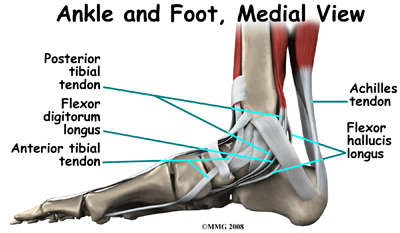

Ligaments are the soft tissues that attach bones to bones. Ligaments are very similar to tendons in their make up however tendons attach muscles to bones rather than bones to other bones. Both of these structures are made up of small fibers of a material called collagen. The collagen fibers are bundled together to form a rope-like structure.

The large Achilles' tendon, at the back of the ankle is the most important tendon for walking, running, and jumping. It attaches the calf muscles to the heel bone to allow us to rise up on our toes. The posterior tibial tendon attaches one of the smaller muscles of the calf to the underside of the foot. This tendon helps support the arch and allows us to turn the foot inward. Failure of the posterior tibial tendon is a major problem in many cases of pes planus.

Many small ligaments hold the bones of the foot together. Most of these ligaments form part of the joint capsule around each of the joints of the foot. A joint capsule is a watertight sac that forms around all of the joints of the foot. The capsule is made up of the ligaments around the joint and the soft tissues between the ligaments that fill in the gaps and form the sac.

The plantar fascia is a thick band of ligamentous tissue on the bottom of the foot that extends from the heel to the toes. When you pull your toes back with one hand, you will be able to feel this band with your fingers of the other hand. This fascia is also critical in supporting the long arch of the foot and in creating the rigid foot structure mentioned above.

The spring ligament complex, which supports the talonavicular joint, is often involved in the flatfoot condition. The spring ligament complex works with the posterior tibial tendon and the plantar fascia to support and stabilize the longitudinal arch of the foot. Laxity of the ligaments that support this arch can result in deformity of the foot and/or ankle resulting in pes planus.